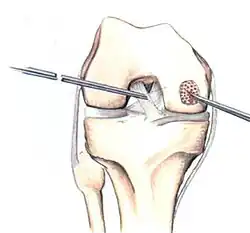

Arthroscopic image of OATS surgery on the medial femoral condyle of the knee

If non-surgical measures are unsuccessful, drilling may be considered to stimulate healing of the subchondral bone. Arthroscopic drilling may be performed by using an antegrade (from the front) approach from the joint space through the articular cartilage, or by using a retrograde (from behind) approach through the bone outside of the joint to avoid penetration of the articular cartilage. This has proven successful with positive results at one-year follow-up with antegrade drilling in nine out of eleven teenagers with the juvenile form of OCD,[53] and in 18 of 20 skeletally immature people (follow-up of five years) who had failed prior conservative programs.[54]